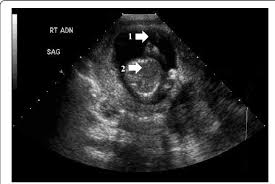

Why You Shouldn T Empty Your Bladder When Preparing For An Ultrasound Independent Imaging

Why You Shouldn T Empty Your Bladder When Preparing For An Ultrasound Independent Imaging from wp02-media.cdn.ihealthspot.com